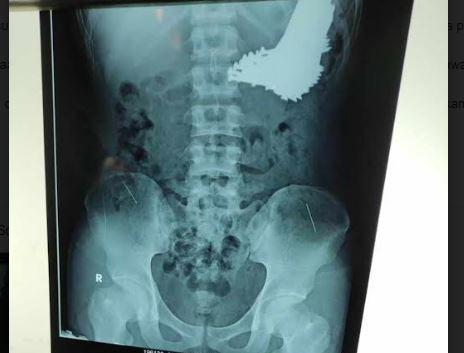

Hal itu diketahui setelah dokter melakukan rontgen terhadap pria berinisial SH (22) yang diduga berstatus orang dalam gangguan jiwa (ODGJ). Dari hasil foto Rontgen itu diketahui ada banyak paku berukuran besar bersarang di dalam lambung korban.

Dari hasil Rontgen tersebut, Deden menyampaikan, terlihat ada benda asing di dalam tubuh pasien yang diduga adalah paku. "Setelah itu, akhirnya dikonsulkan ke dokter spesialis bedah, dan kemudian untuk diadvis untuk dilakukan operasi segera," ujar dia.

Salah satu dokter spesialis bedah yang menangani pasien tersebut langsung mengambil tindakan operasi selama dua jam. Dari hasil tindakan cepat itu, didapati sebanyak 70 batang paku yang sudah masuk ke dalam lambung si pasien.